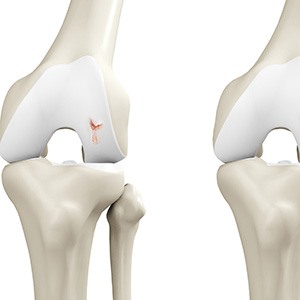

Cartilage Microfracture

Cartilage microfracture is a surgical procedure performed to replace the worn-out articular cartilage with new cartilage.